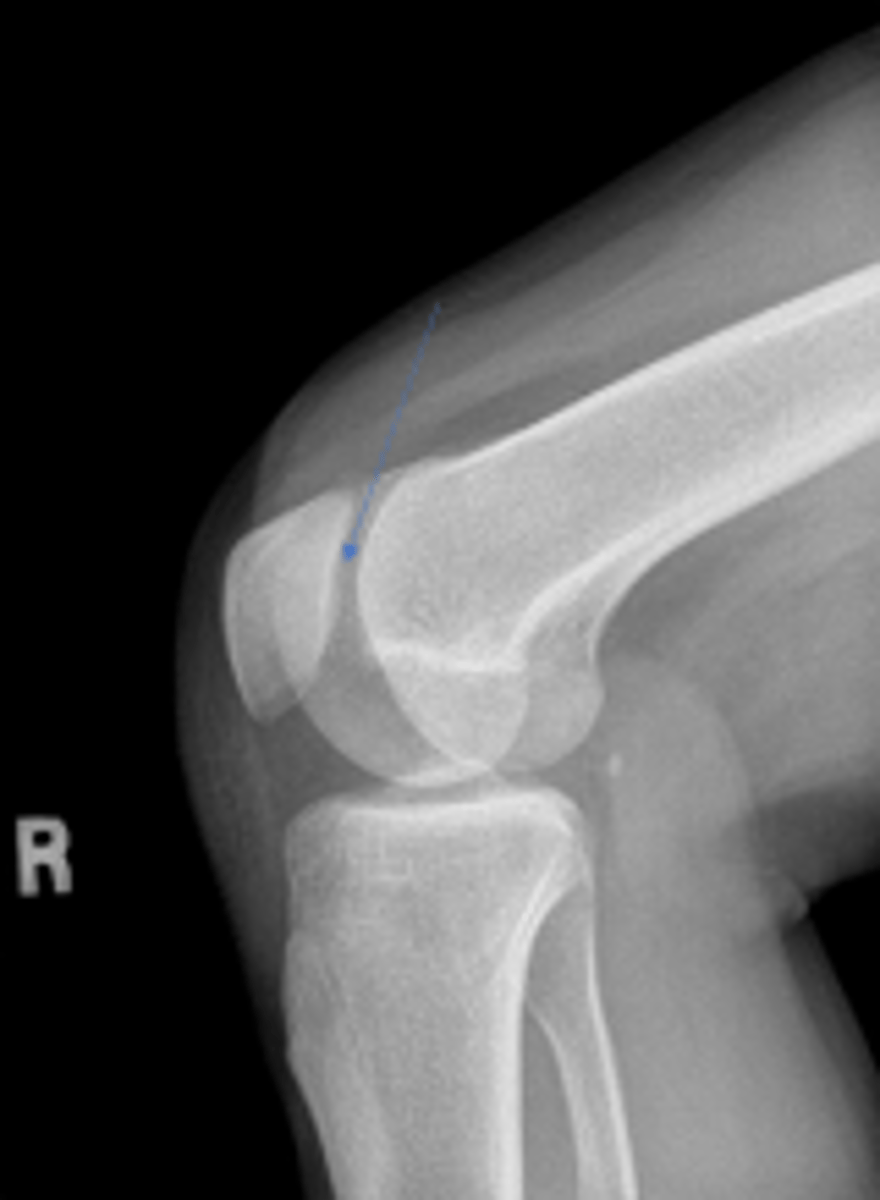

What is the name of the radiographic view?

Right internal oblique knee

What tubercle is pointed to by the arrow?

Lateral epicondyle of the right femur

What is the arrow pointing to?

Medial epicondyle of the right femur